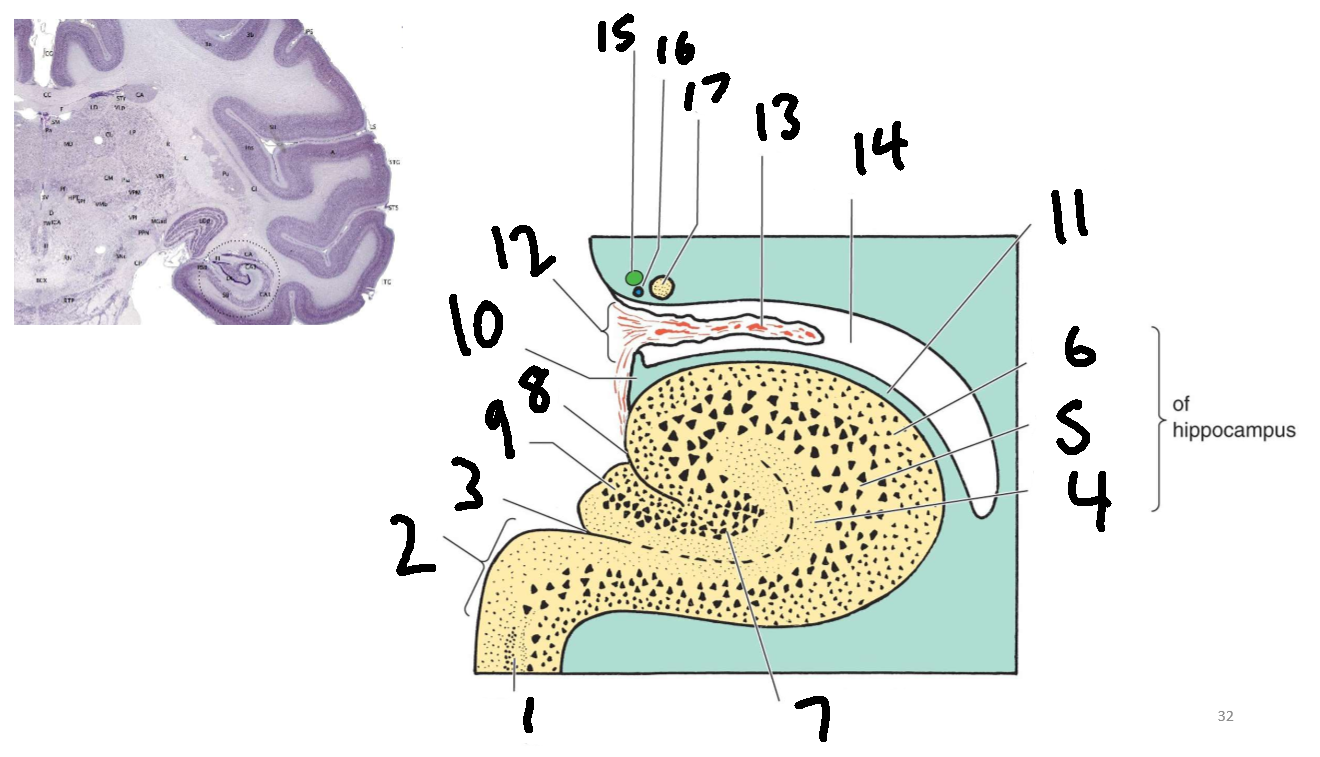

What is 1?

parahippocampal gyrus

What is 2?

subiculum

What is 3?

hippocampal sulcus

What is 4?

molecular layer

What is 5?

pyramidal layer

What is 6?

polymorphic cell layer

What is 7?

granule cell layer of dentate gyrus

What is 8?

fimbriodentate sulcus

What is 9?

dentate gyrus

What is 10?

fimbria of hippocampus

What is 11?

alveus

What is 12?

choroid fissure

What is 13?

choroid plexus

What is 14?

temporal horn of lateral ventricle

What is 15?

stria terminalis

What is 16?

thalamostriate vein

What is 17?

tail of caudate nucleus